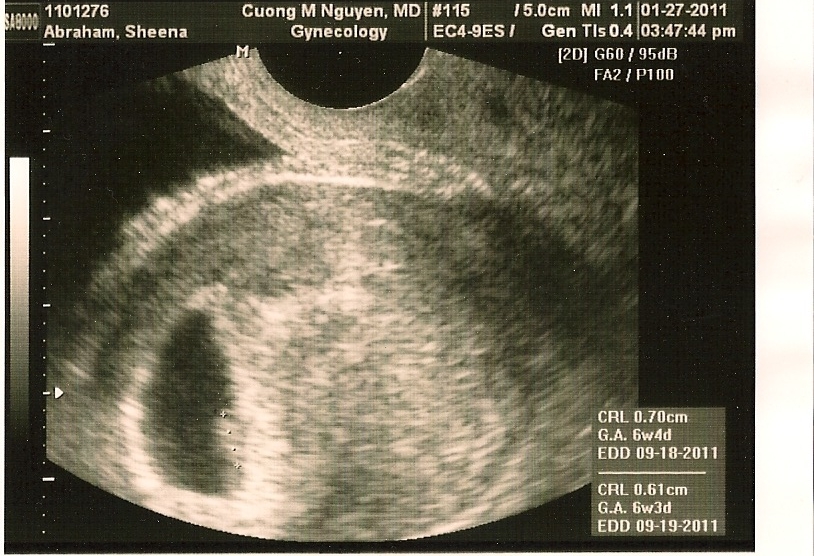

Here’s Muttoncurry’s first baby pic: